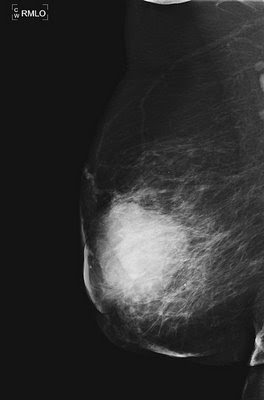

Характеристики маммографического риска рака молочной железы